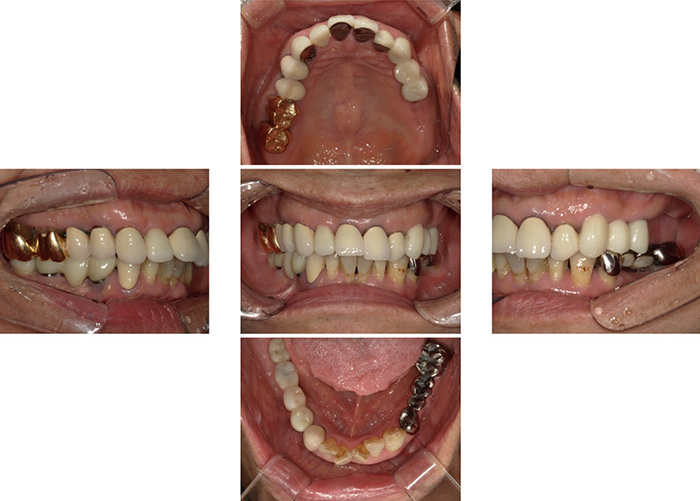

Case.10

![]() |

|---|

| 主訴 | 左上は骨がないからインプラントができないといわれた。 |

|---|---|

| 治療期間 | 6か月 |

| 治療費 | 200,000円(骨造成:サイナスリフト ラテラルアプローチ) |

| 治療内容 | 骨を増やす治療です。 人工の骨を入れて不足した骨を増生します。 |

| 治療のリスク | 一時的な鼻出血、内出血、眼出血、上顎洞炎、腫脹のリスクがあります。 |